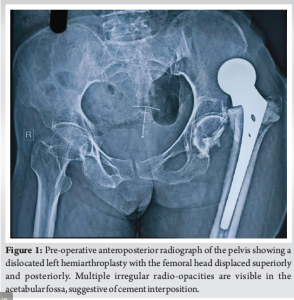

A 76-year-old female patient underwent a left Non-modular unipolar hemiarthroplasty 8 months ago in view of fracture neck of femur, based on the previous scar the procedure was performed through a posterior approach. The patient was able to walk with the help of a walker for 1 month post-surgery after which the patient experienced a sudden shift or slipping sensation in the hip, followed by pain and difficulty moving. At the time of the slippage, the patient did not seek immediate medical attention. Due to limited mobility and lack of access to local orthopedic care, she remained bedridden at home and received only symptomatic treatment in the form of analgesics prescribed by a local physician. No radiographic evaluation or surgical consultation was done until she presented to our outpatient department 8 months post-surgery with chief complaints of persistent left hip pain and restricted mobility and function of the left hip. She was unable to bear weight on her left limb and was bedridden for 7 months. On clinical examination, the left leg was shortened with a limb length discrepancy of 4 cm and was fixed in adduction and internal rotation. The patient was sent for radiographic examination, and a dislocated left hip was confirmed, additionally, they revealed multiple irregular radio-opacities in the acetabular fossa, raising suspicion of cement interposition, retained bony fragments, or intra-articular ossification. The opacities varied in density, with some areas appearing homogeneous and others more fragmented (Fig. 1). A computed tomography scan was considered to better assess cement penetration, retained bone fragments, and acetabular integrity. However, due to financial constraints, further imaging was not pursued. The surgical plan was formulated based on clinical findings and standard radiographs, with intraoperative evaluation guiding implant selection. Pre-operatively, a percutaneous adductor tenotomy was performed to release contractures caused by the chronic dislocation. In addition, skin traction was applied for 2 weeks to help gradually correct limb alignment, reduce muscle stiffness, and facilitate intraoperative reduction. A posterior approach was selected to facilitate access to both the acetabulum and femoral canal while ensuring adequate visualization. Intraoperatively, a well-formed cement mantle was identified conforming to the acetabular shape, confirming cement migration as the underlying pathology. No bony remnants or free-floating osteochondral fragments were observed, effectively ruling out residual femoral head fragments and intra-articular loose bodies. The acetabular walls were intact, and no signs of osteolysis, sequestrum, or infection were observed. The extracted cement was removed en bloc (Fig. 2). A bipolar prosthesis was chosen over total hip replacement (THR) due to the patient’s advanced age, lower functional demands, and intact acetabular wall with no significant erosion or osteolysis. In contrast to the index surgery, meticulous cementing technique was followed. The acetabulum was protected using moist gauze to prevent cement entry, and the cement was introduced only in its doughy phase. The femoral canal was thoroughly prepared, and cement was introduced retrograde with controlled pressurization to achieve a uniform mantle and secure implant fixation. The hip was successfully reduced, ensuring good stability and range of motion (Fig. 3). Given the patient’s advanced age and osteoporotic bone quality, prophylactic cerclage wiring was applied in the subtrochanteric region to reinforce the femur and minimize the risk of intraoperative or post-operative periprosthetic fracture. Thorough irrigation to minimize the risk of infection, careful soft tissue balancing to optimize hip biomechanics, and repair of the posterior capsule to enhance stability were done. Intraoperative assessment confirmed satisfactory positioning of the prosthesis with no undue impingement or instability. Closure was performed in layers, and the patient was stabilized post-operatively. Standard operating procedures were maintained. The immediate post-operative radiograph demonstrated a well-seated bipolar prosthesis with concentric reduction of the hip joint. The acetabular contours appeared intact with no residual cement fragments or signs of joint incongruity. Limb alignment was restored with no limb length discrepancy, and the implant position was stable without evidence of subsidence or malposition (Fig. 4). The patient had a smooth recovery and was discharged 2 weeks after surgery with instructions for partial weight-bearing using bilateral axillary crutches and focusing on restoring hip mobility and muscle strength.